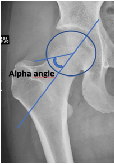

Prevalence of Abnormal Hip Alpha Angle in Football Players- A Potential Contributory Factor to Other Pathologies